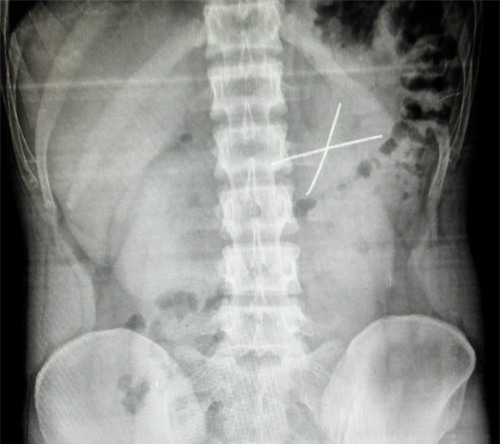

Kết quả X-quang bụng cho thấy dị vật có dạng chữ X.

Trước đó, bệnh nhân nhập viện vì đau bụng dữ dội, xuất huyết tiêu hóa, kết quả chụp X-quang bụng cho thấy hình ảnh cản quang có dạng chữ X ở ¼ phía trên bên phải vùng bụng. Nội soi dạ dày tá tràng phát hiện có hai cọng dây kẽm cột dây thun bắt chéo, hai đầu cắm vào niêm mạc dạ dày bệnh nhân. Do vậy các bác sỹ không thể gắp trực tiếp qua nội soi mà phải phẫu thuật “cứu” nạn nhân.

Hai đoạn dây kẽm dài 8cm được lấy ra ngoài